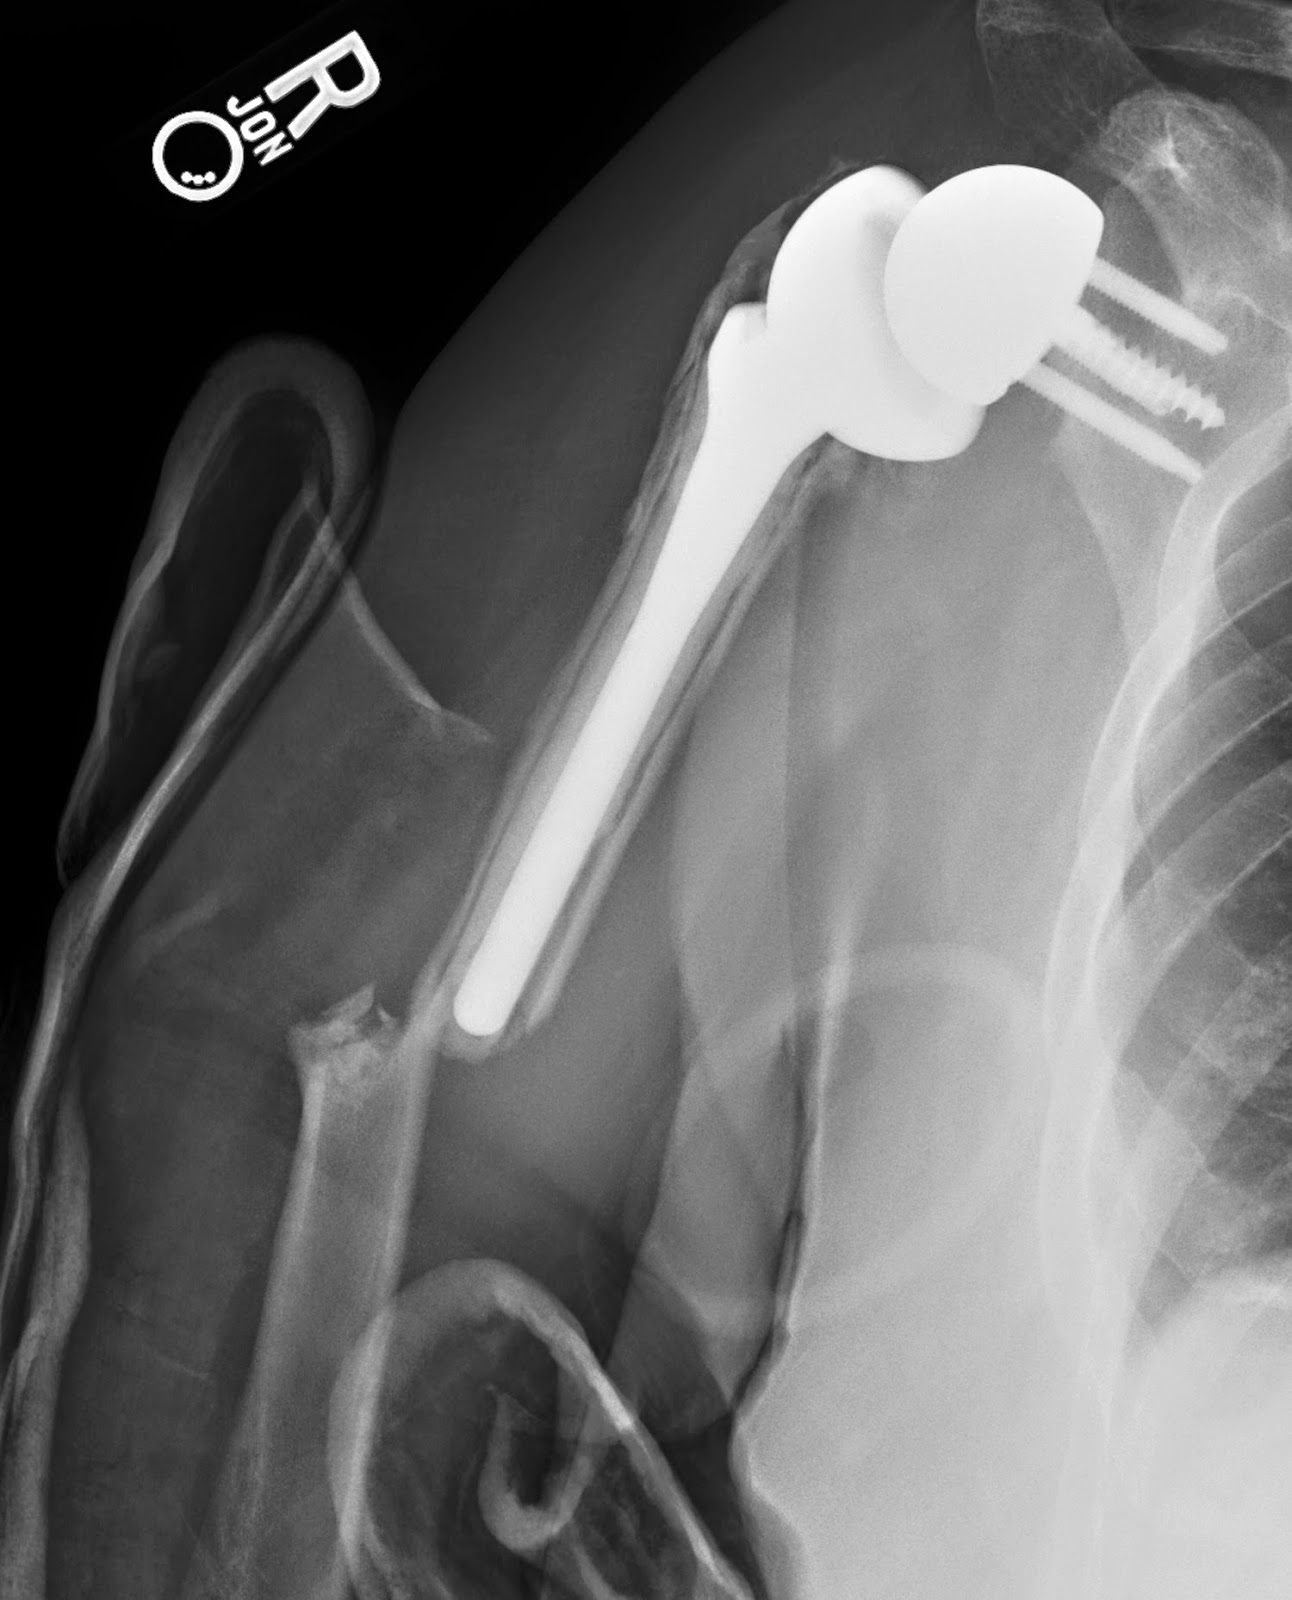

Reverse shoulder replacement dislocation Image Is A Reverse Shoulder Replacement Very Painful If the rotator cuff tendons are. a reverse prosthesis can significantly reduce pain and restore some range of motion in the shoulder. some of the potential risks associated with a reverse shoulder replacement include: reverse shoulder replacement may be a better way to improve the joints function and reduce pain, especially if the joint is affected by.. Is A Reverse Shoulder Replacement Very Painful.